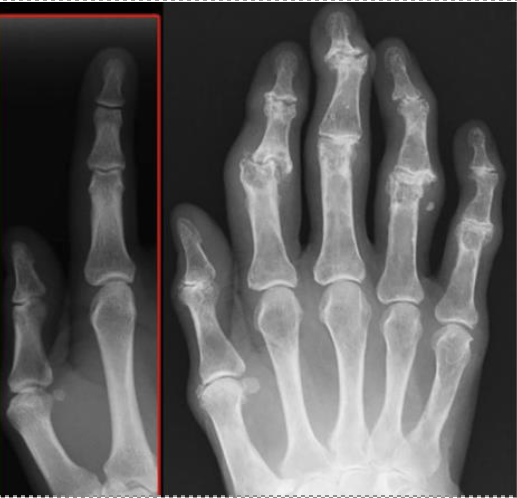

Osteoarthritis can cause inflammation of the joints in the hands. Heberden nodes are present in the joint at the end of the finger, called the distal interphalangeal joint. Bouchard nodes are present in the middle joint of the finger, called proximal interphalangeal joint. J. Lengerke 21:37, 27. Mai 2009 (CEST), CC BY-SA 3.0 DE